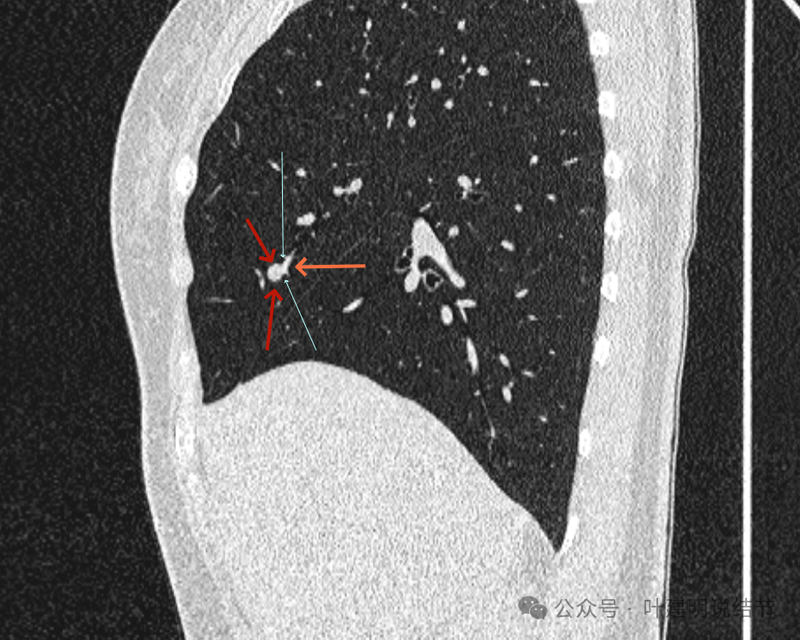

血管贴着,结节膨胀。

也示血管与病灶的关系。

结节实性。

纵隔窗这个角度明显见到蓝色箭头所指的血管被病灶侵蚀,而且血管与病灶密度的不同。